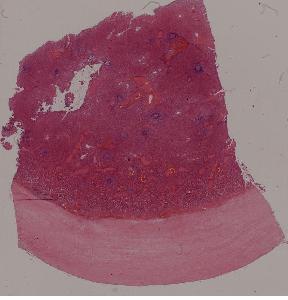

4.脾包膜玻璃样变

低倍视野